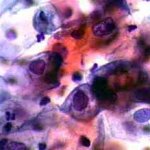

Δυσπλασίες τραχήλου μήτρας σοβαρού βαθμού (CIN III)

Ασυμπτωματική ασθενής 39 ετών. PH κόλπου 4,4. Κολποσκόπιση:

Στην δοκιμασία οξικού οξέως και στην δοκιμασία Lugol, αρνητική περιοχή, τόσο στο πρόσθιο, όσο και στο οπίσθιο χείλος του τραχήλου, σε ακτίνα 3-4 χιλ. και πλάτος περίπου 5 χιλ., με εικόνα διακριτικού επίπεδου μωσαϊκού.